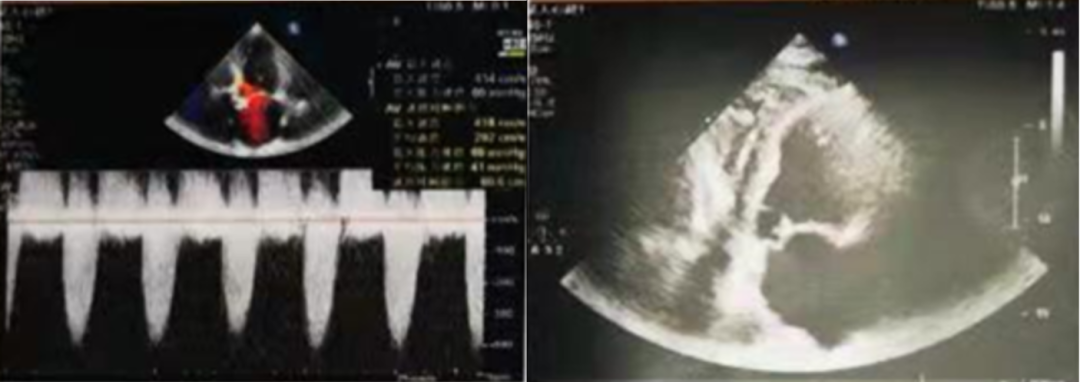

2022年1月25日超声图像

主动脉瓣峰值流速:4.14M/S;平均跨瓣压差:69mmHg;左室射血分数EF值:29%。

2022年2月13日超声图像

主动脉瓣峰值流速:4.59M/s;

升主动脉内径:55mm;

平均跨瓣压差:84mmHg;

左室射血分数EF值:46%;

主动脉瓣增厚,回声增强,瓣叶形态显示不清,瓣膜开放明显受限;

升主动脉瘤形成;心包积液;

主动脉瓣口左室流出道侧见舒张期轻度反流信号。

诊断:主动脉瓣重度狭窄。经团队讨论和患者家属商议后决定,行TAVR手术治疗。

2022年2月24日术后超声图像

术后改善明显:

主动脉瓣峰值流速从4.59M/s降至2.12M/s;

平均跨瓣压差从84mmHg降至18mmHg;

升主动脉内径从55mm降至52mm

左室射血分数EF值从46%升至52%